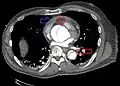

Computed tomography

Computed tomography angiography is a fast, non-invasive test that gives an accurate three-dimensional view of the aorta. These images are produced by taking rapid, thin-cut slices of the chest and abdomen, and combining them in the computer to create cross-sectional slices. To delineate the aorta to the accuracy necessary to make the proper diagnosis, an iodinated contrast material is injected into a peripheral vein. Contrast is injected and the scan performed using a bolus tracking method. This type of scan is timed to injection to capture the contrast as it enters the aorta. The scan then follows the contrast as it flows through the vessel. It has a sensitivity of 96 to 100% and a specificity of 96 to 100%. Disadvantages include the need for iodinated contrast material and the inability to diagnose the site of the intimal tear.

CT with contrast demonstrating aneurysmal dilation and a dissection of the ascending aorta (type A Stanford)

CT with contrast demonstrating aneurysmal dilation and a dissection of the ascending aorta (type A Stanford)_Aortic_Dissection.PNG.webp) Chest CT with descending (type B Stanford) aortic dissection (red circle)

Chest CT with descending (type B Stanford) aortic dissection (red circle) Type A dissection with pericardial effusion as a result.

Type A dissection with pericardial effusion as a result.